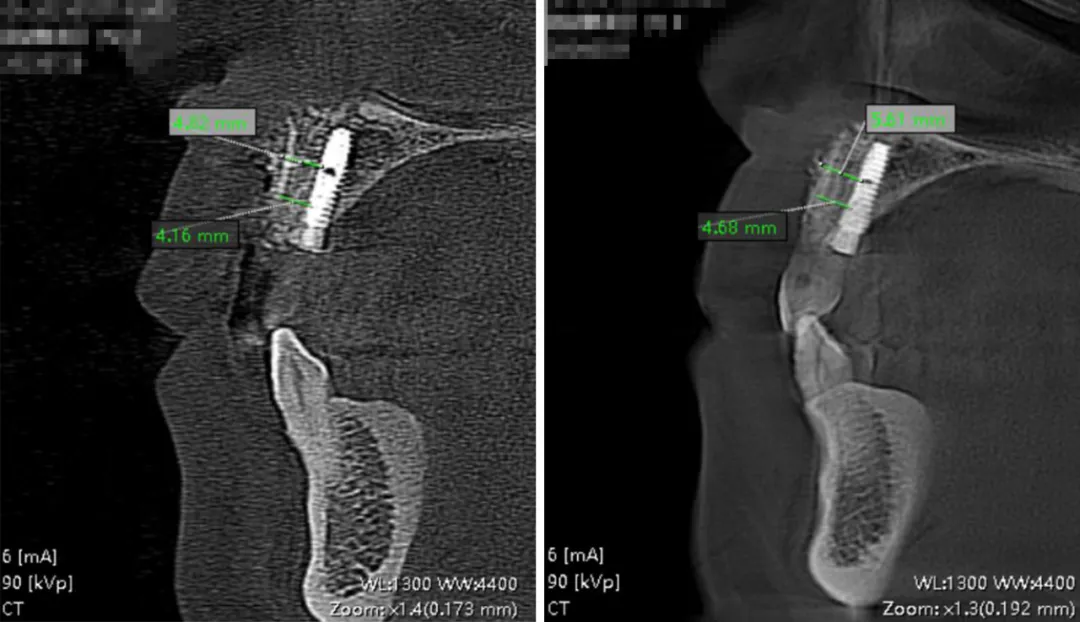

影像学检查

术前与术后影响对比,骨片的屏障维持效果理想,颊舌向骨量宽度维持在 10.35mm 左右

11 牙位屏障维持稳定,8 个月时水平向骨量维持在 4.5mm 左右

21牙位屏障维持稳定,8 个月时水平向骨量维持在 3.8mm 左右